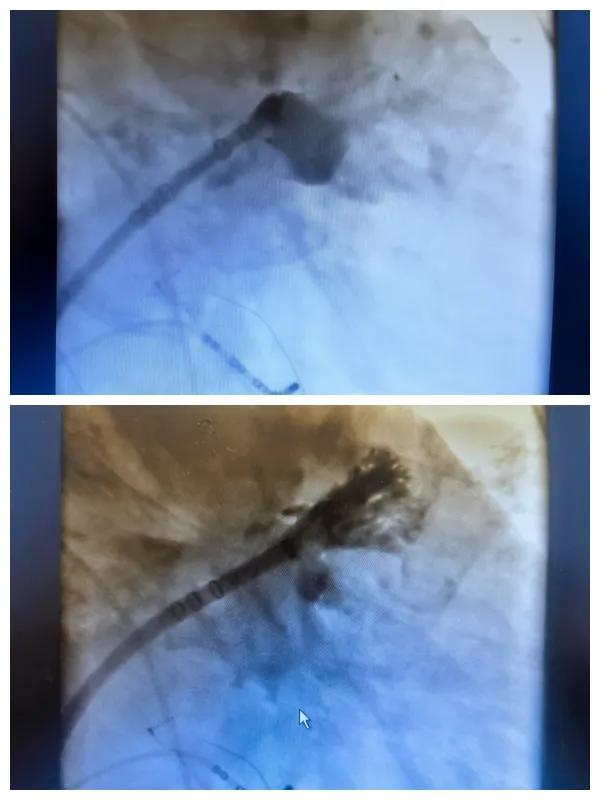

漯河市二院成功開(kāi)展房顫射頻消融術(shù)+左心耳封堵WM FLX一站式手術(shù),再攀“心”高峰!

房顫射頻消融術(shù)+左心耳封堵WM FLX一站式手術(shù)

6月26日,市二院成功為一名老年房顫患者實(shí)施了房顫射頻消融術(shù)+左心耳封堵WM FLX一站式介入治療,標(biāo)志著醫(yī)院在心律失常介入治療領(lǐng)域邁出了嶄新的一步,開(kāi)啟了新的治療篇章。

本次手術(shù)特邀我國(guó)著名心血管內(nèi)科專家、河南省胸科醫(yī)院黨委書(shū)記袁義強(qiáng)及血管內(nèi)科七病區(qū)主任黃瓊教授蒞臨指導(dǎo),市二院院長(zhǎng)王瑾帶領(lǐng)心血管內(nèi)科電生理等專家團(tuán)隊(duì)緊密合作,一次性解決了患者房顫、血栓兩大困擾,也使患者告別了終身服用抗凝藥的痛苦,極大地降低了患者的經(jīng)濟(jì)和用藥負(fù)擔(dān)。

為了讓患者得到全面、綜合的治療,經(jīng)過(guò)團(tuán)隊(duì)術(shù)前充分討論,并征得家屬同意,心血管內(nèi)科團(tuán)隊(duì)決定采用目前國(guó)內(nèi)外先進(jìn)的房顫射頻消融術(shù)+左心耳封堵WM FLX一站式介入微創(chuàng)手術(shù)來(lái)治療老人的疾病。整個(gè)手術(shù)過(guò)程圓滿順利,術(shù)后何大爺各項(xiàng)體征正常,蘇醒后順利返回病房。